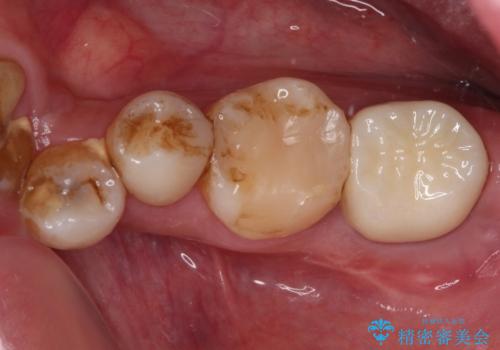

欠損と痛み 奥歯のむし歯治療